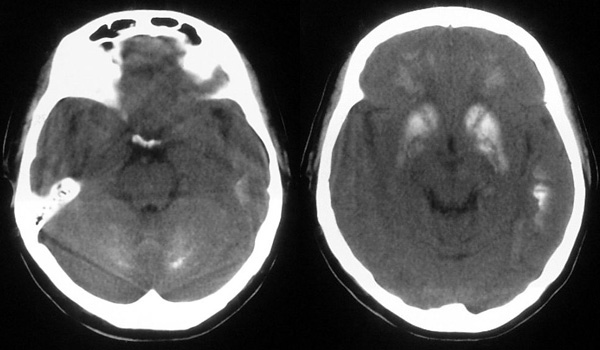

患者,女,49岁,头痛数年,有癫痫病史,无外伤史。

甲状旁腺低下:颅脑 ct 可见以基底节为中心的双侧对称性、多发性、多形性脑钙化的特点。除苍白球外,可广泛分布于壳核、尾状核、小脑齿状核、丘核、内囊及脑皮质、白质等处。